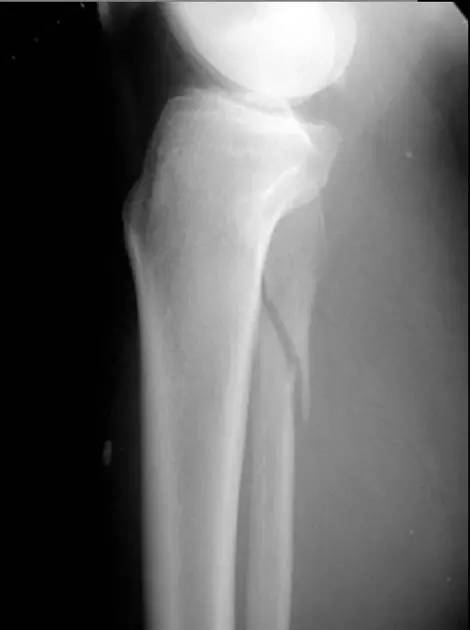

儿童骺 Salter-Harris 骨折

随着年轻人越来越多地参加对抗性运动,骨科医生遇到的青少年骨折也日渐频繁。来诊的常常是轮滑爱好者或者在球类竞技受伤。年轻患者骨骼多见「青枝骨折」,这就像嫩树枝可以折而不断。而骨骼生长板(即骺板)还没闭合的孩子,常常会出现骨骺损伤,对此损伤一般国际上通用 Salter Harris 分型。